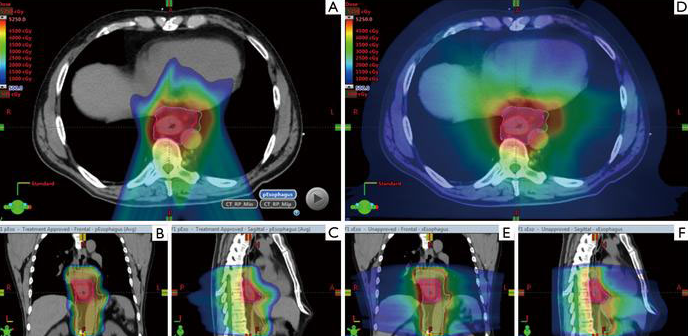

因此,質子治療憑借特殊的“布拉格峰效應”,為食管癌的治療提供了便利。與光子放療相比,質子治療可以減少心肺等風險器官的輻射劑量,降低并發癥,同時無需降低針對腫瘤的輻射劑量,提高食管癌的治愈率。

▲質子治療食管癌,